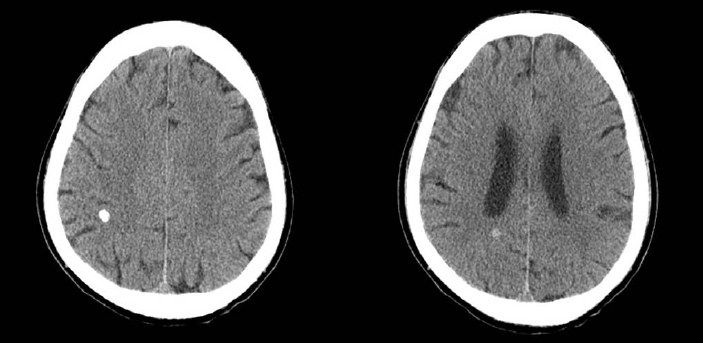

방사선 검사 소견: 뇌전산화 단층촬영에서 우 두정엽에 두 개의 석회화 병변이 관찰되었다(Fig. 1).

Figure 1.

Pre-enhancement computed tomography scan of the brain shows two high density lesions in the right parietal area.

본 증례는 당뇨병의 병력이 없던 사람이 간질 지속증으로 내원하여 NKH를 진단 받은 경우로 본 증례와 같이 전신 경련성 간질 지속증으로 발현한 NKH는 보고된 것이 많지 않다. 국내에서는 유일하게 Lee 등[10]이 전신 경련성 간질 지속증으로 발현된 NKH 3예를 보고한 바 있다. 전신 경련성 간질 지속증을 일으킬 수 있는 원인으로 외상, 뇌혈관질환, 뇌종양, 중추신경계 감염 등이 있으나[8], 본 증례의 경우에는 이에 해당하는 병력, 임상상 혹은 검사 결과가 없었다. 뇌전산화 단층촬영에서 석회화 병변이 관찰되었지만 병변의 위치나 혈당 조절 이후에 경련 발작이 조절된 점으로 볼 때 본 증례의 경우 전신 경련성 간질 지속증의 원인이 NKH일 가능성이 가장 높다.